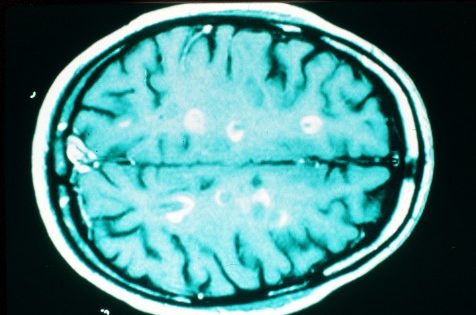

La pérdida de funciones físicas y cognitivas tiene su origen en dos tipos de daño que provocan la pérdida de neuronas y tejido cerebral: lesiones inflamatorias focales (daño focal) y procesos neurodegenerativos más generalizados (daño difuso). Las lesiones inflamatorias focales pueden presentarse clínicamente como recaídas y contribuir a generar discapacidad. El daño difuso se manifiesta al inicio de la enfermedad, a menudo no es perceptible y se relaciona con la pérdida de volumen cerebral y la acumulación de discapacidad irreversible.

Para el seguimiento de la EM los expertos destacan cuatro aspectos clave: los brotes, la actividad en Resonancia Magnética, la acumulación de discapacidad y la pérdida de volumen cerebral. “Cuando un paciente consigue un control de estos parámetros, es decir una falta de evidencia de actividad de la enfermedad (NEDA), se confirma que está siendo abordado con el tratamiento adecuado” explica el doctor Rafael Arroyo, coordinador de Esclerosis Múltiple del Hospital Clínico San Carlos de Madrid.

Entre los aspectos clave, la pérdida de volumen cerebral se está convirtiendo en un marcador importante de progresión de la discapacidad a largo plazo, y es una cuestión de gran interés dentro de la comunidad médica especializada en esta patología. Estudios recientes encuentran una correlación entre la pérdida de volumen cerebral (atrofia cerebral) y un aumento en el riesgo de recaídas y progreso de la discapacidad.

Los pacientes con EM pierden volumen cerebral aproximadamente de tres a cinco veces más rápido que las personas sin esta patología. Esta pérdida se produce de forma precoz, prosigue durante el curso de la enfermedad, y se ha asociado también con la disfunción cognitiva además de con la física (discapacidad).

El interés de utilizar el volumen cerebral como marcador de atrofia cerebral se ha incrementado en los últimos años, debido al desarrollo de nuevos tratamientos con un potencial efecto neuroprotector o neurorreparador” explica la doctora Cristina Auger, de la Unidad de Resonancia Magnética del Servicio de Radiología del Hospital Universitario Vall d’Hebron, de Barcelona.

La EM es una enfermedad con dos componentes, uno inflamatorio y otro neurodegenerativo y para analizar este último es necesario utilizar resonancia magnética.

en los últimos años se está realizando un gran esfuerzo en el desarrollo y aplicación de técnicas de RM que permiten detectar de forma específica, sencilla y reproducible aquella afección macro o microscópica que se relaciona con el grado de discapacidad clínica”, explica la doctora Auger.